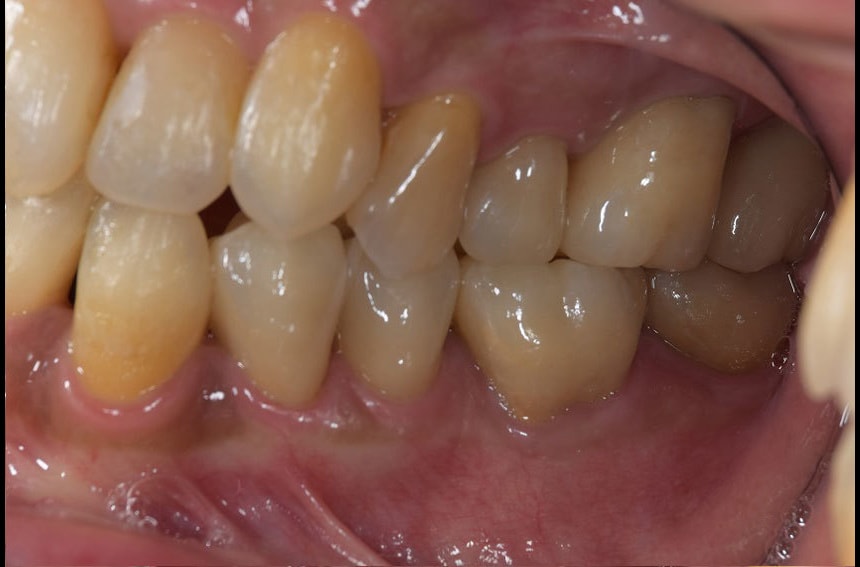

右奥歯の治療前後

左奥歯の治療前後

最小限の矯正治療や過去に治療した銀歯の隙間から虫歯になった歯や神経の再治療を行いました。もう少し修正が必要なのですが、部分矯正も含め長い治療になり、とりあえずはお疲れさまでした。